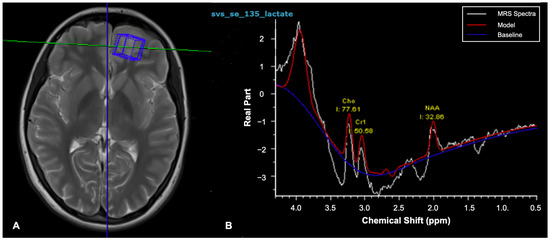

- Manias, K.A.; Peet, A. What is MR spectroscopy? Arch. Dis. Child Educ. Pract. Ed. 2018, 103, 213–216. [Google Scholar] [CrossRef] [PubMed]

- Liserre, R.; Pinelli, L.; Gasparotti, R. MR spectroscopy in pediatric neuroradiology. Transl. Pediatr. 2021, 10, 1169–1200. [Google Scholar] [CrossRef] [PubMed]